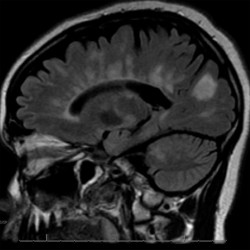

- MRI imaging with contrast is the most important imaging modality in the workup of possible MS.

- Demyelinating lesions related to MS are ovoid, >3 mm in diameter, and are typically located in particular regions: periventricular (Dawson’s fingers), juxtacortical, cortical, or spinal cord.